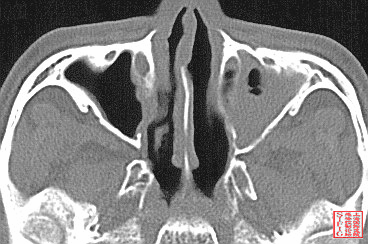

1990年RCT研究显示,鼻窦炎发生率,经鼻插管者(43.1%)显著高于经口插管(1.8%)。

Prospective RCT of 111 pts, randomized to either orotracheal or nasotracheal intubation; All had a nasogastric feeding tube. Primary outcome: incidence of maxillary sinusitis by radiography (Waters' view) at the bedside. Maxillary sinusitis occurred in 1/53 (1.8%) of the orotracheal group (on the nasogastric tube side), and in 25/58 (43.1%) of the nasotracheal group (7 on the nasogastric tube side, 11 on the endotracheal tube side, 7 bilateral; p less than 0.001). long-term orotracheal intubation reduced significantly the incidence of maxillary sinusitis in comparison with nasotracheal intubation.